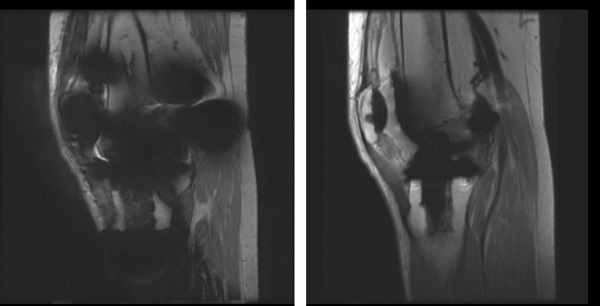

Metal artifact

When MR conditional metal implants are present, various artifacts including ringing, stripe, signal void and image distortion are observed. The one-click application, MAVRIC SL, can reduce the artifacts but cannot completely remove them.

| Left | Image acquired with 2D FSE. Note the image void and distortion around the MR conditional metal implant. |

| Right | Image acquired with MAVRIC SL. Note the reduced signal void around the MR conditional metal implant. |